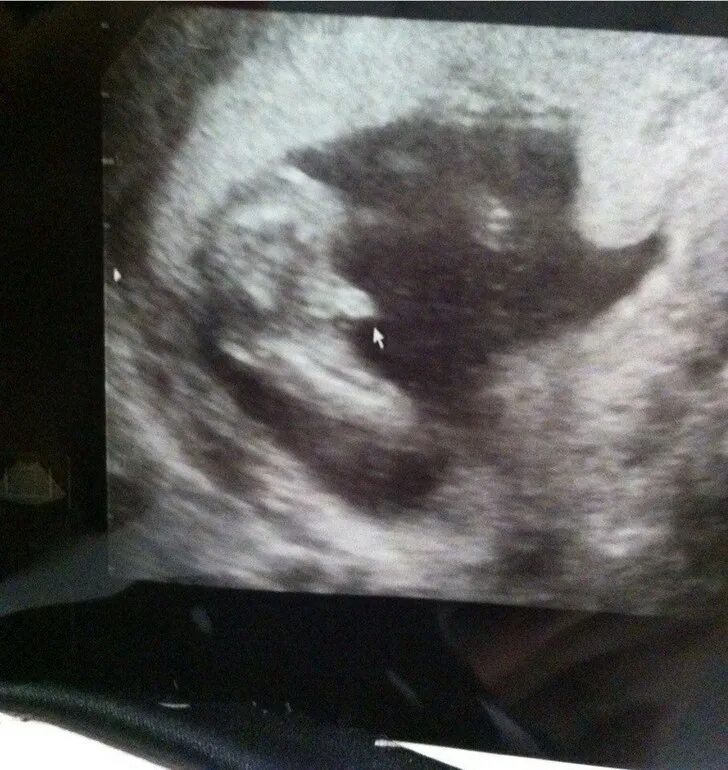

Узи 17 недель девочка